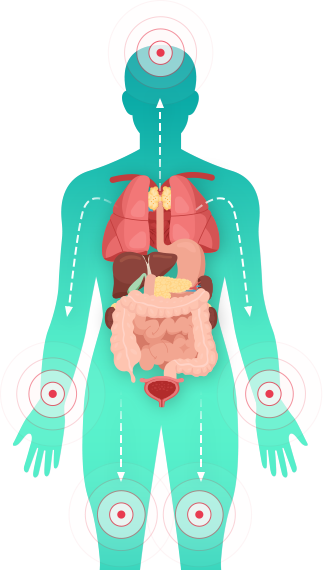

아토피의 발생 원인

생기한의원은 수많은 케이스의 진료와 네트워크 연구 활동을 통해

인체 전반적인 면역의 문제로 발생하는 종합면역질환으로 판단하고 진료합니다.

(현대 의학에서 아직 명확한 원인은 밝혀지지 않았습니다.)

인사이드 아웃(inside-out)

인체 면역 밸런스가 무너져 피부증상으로 발현되는 자가면역 질환으로

판단하는 것으로 소화기관, 폐, 기관지 등 주요 장기의 기능이 원활하지

못한 것이 가장 큰 원인

아웃사이드 인(outside-in)

다양한 이유로 손상된 피부 장벽이 바이러스, 세균, 진균, 알러지 요인들을

막지 못해 쉽게 피부를 뚫고 인체 내부까지 침투하여

피부질환을 일으키는 것이 원인